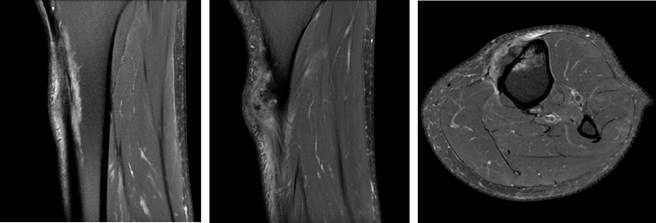

Initially a XR, CT and MR were performed showing a soft tissue tumor on the proximal aspect of the left tibia just inferior to the tibial tuberosity, size of 40 × 29 × 19 mm (coronal × sagittal × axial). Emerging from the anterior tibia periosteum and growing towards the subcutaneous tissue, hyperintense in T2 and hypointense in T1. Tumor presents with irregular and extensive internal calcifications (Figure 2). An initial biopsy was performed that was inconclusive, so an ultrasound guided biopsy was done afterwards with a 14G needle. The pathologist could not conclude between, hypertrophic fracture callus, osteoblastoma or osteosarcoma subtype osteoblastoma.

Figure 2: MR image of the tumor showing growth from the anterior periosteum and internal calcification. Soft tissue invasion can be seen.